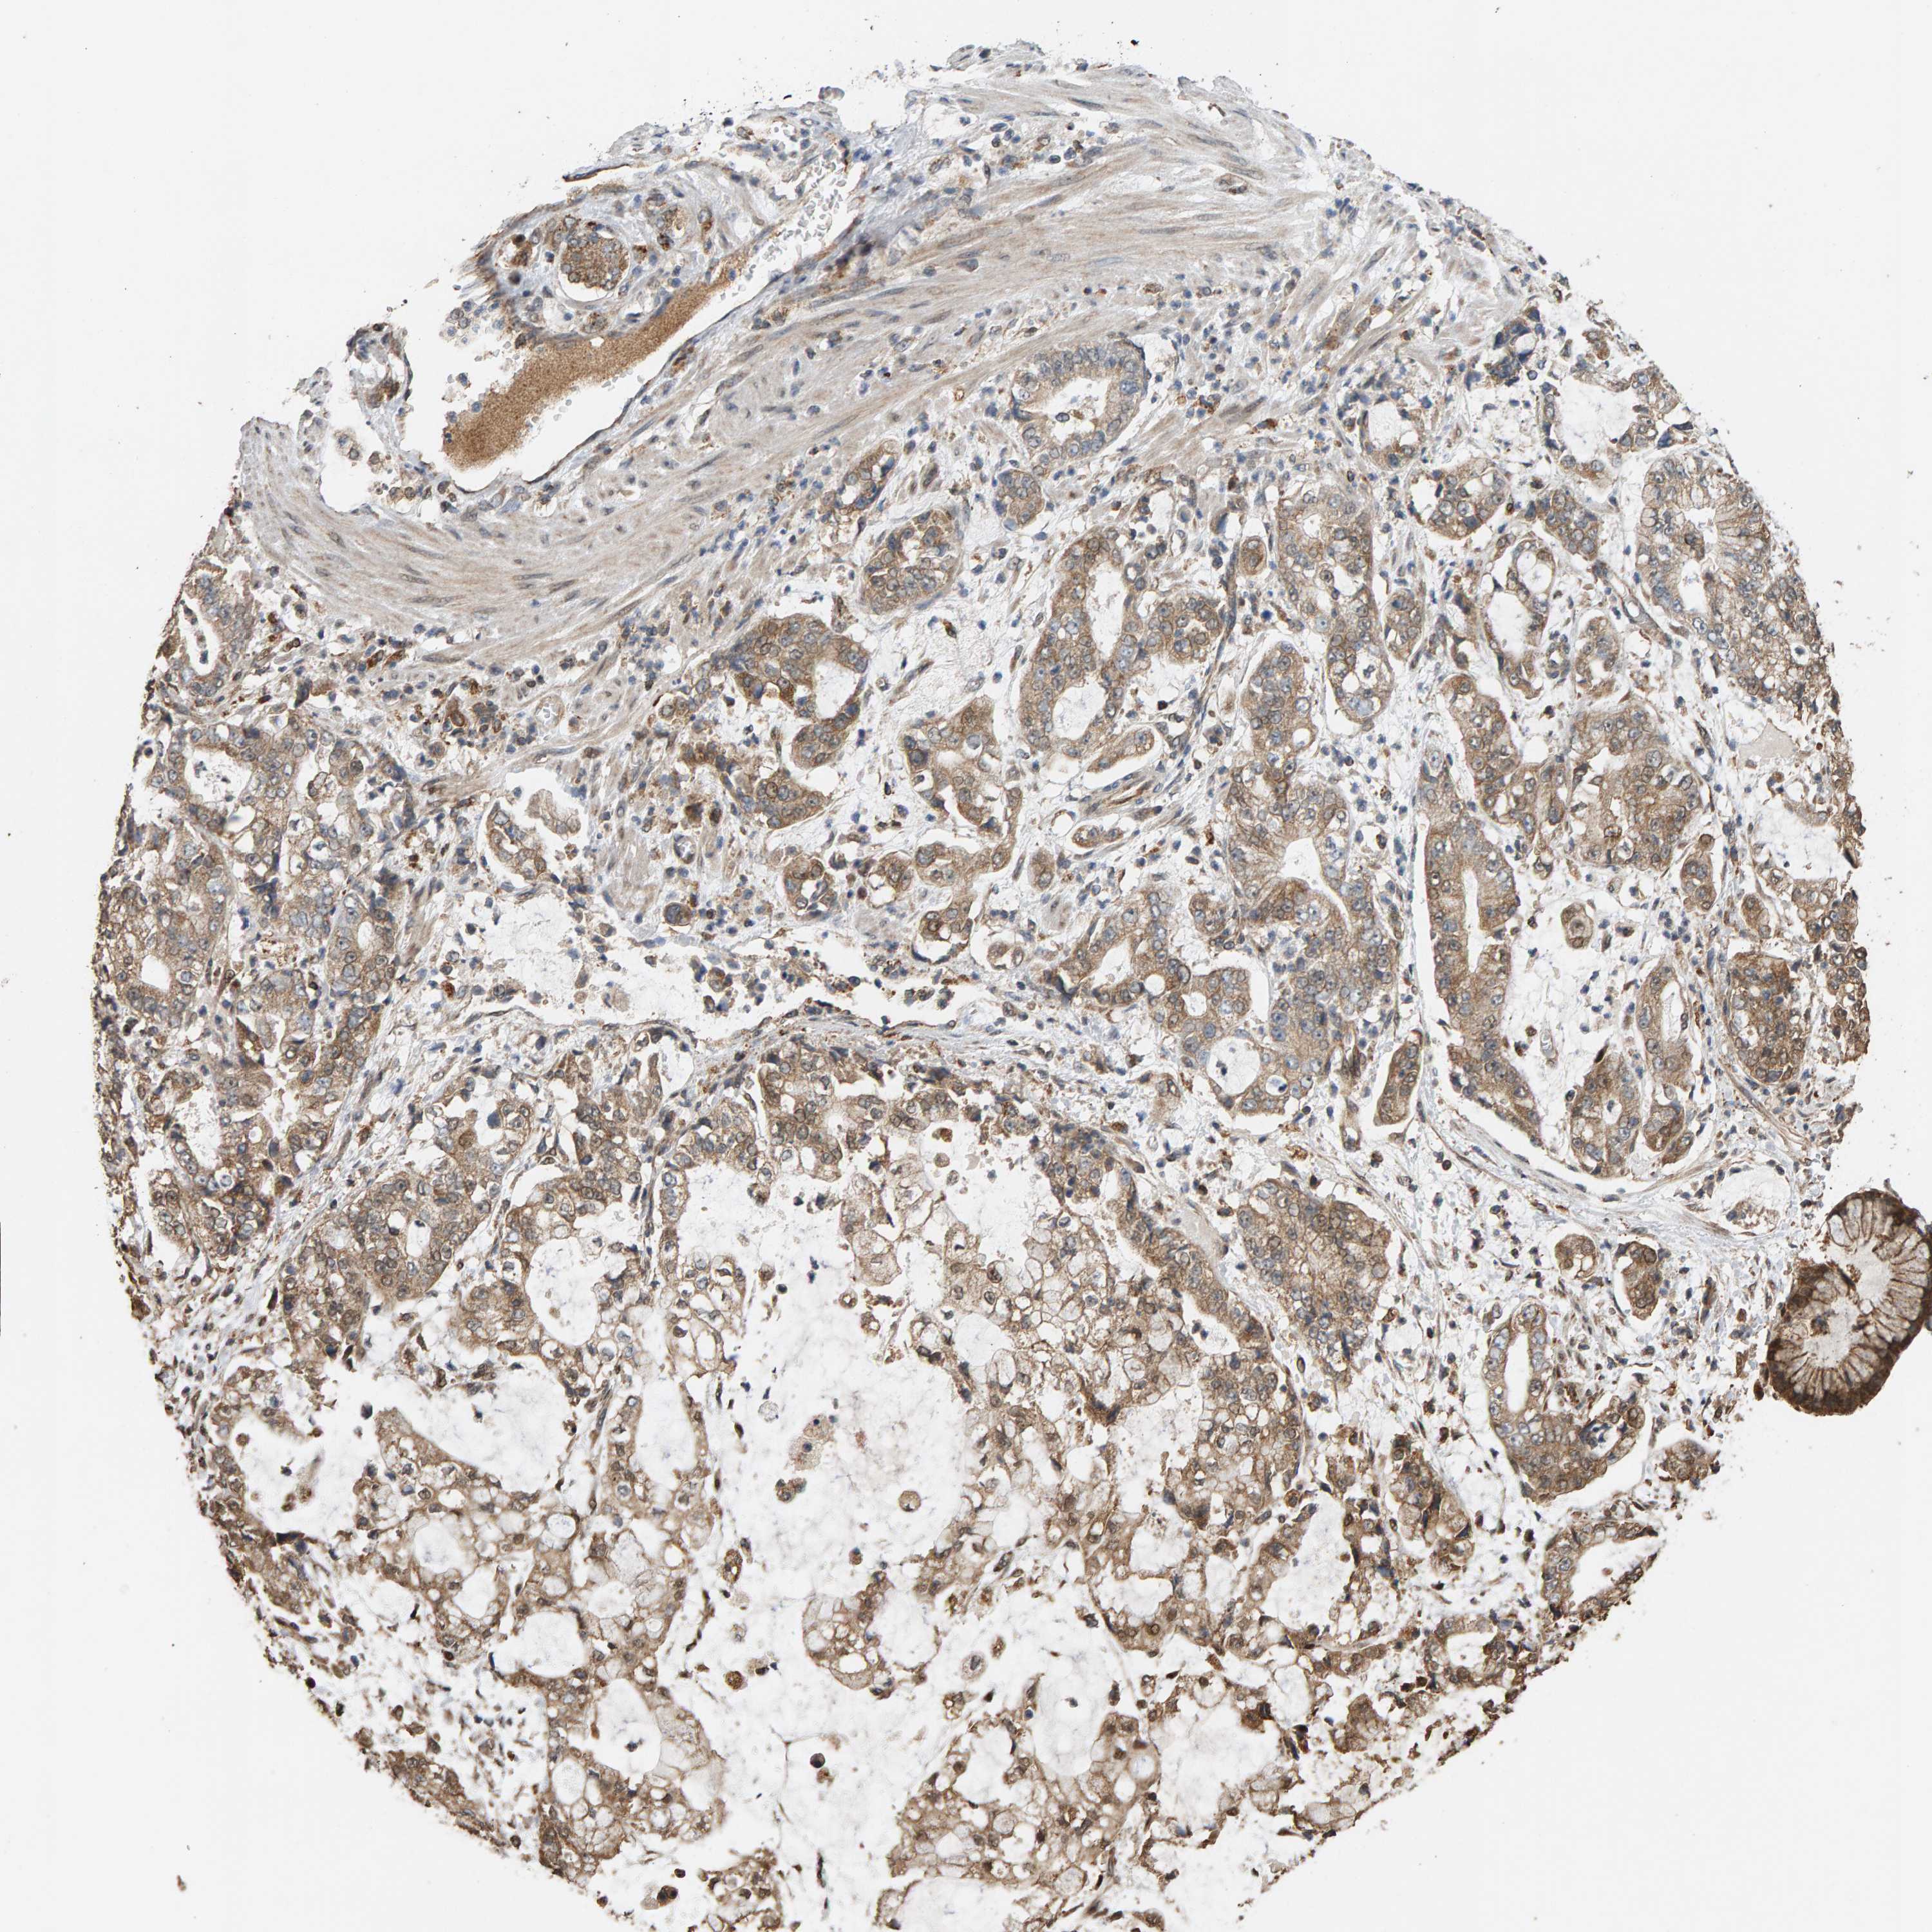

STOMACH CANCER - Protein expressioni

A mouse-over function shows sample information and annotation data. Click on an image to view it in a full screen mode. Samples can be filtered based on level of antibody staining by selecting one or several of the following categories: high, medium, low and not detected. The assay and annotation is described here.

Note that samples used for immunohistochemistry by the Human Protein Atlas do not correspond to samples in the TCGA dataset.

Antibody stainingi

Antibody staining in the annotated cell types in the current human tissue is reported as not detected, low, medium, or high, based on conventional immunohistochemistry profiling in selected tissues. This score is based on the combination of the staining intensity and fraction of stained cells.

Each image is clickable and will lead to virtual microscopy that enables deeper exploration of all samples and also displays staining intensity scores, fraction scores and subcellular localization as well as patient and tissue information for each sample.

Antibody HPA006311

Antibody HPA022904

Staining

High

Medium

Low

Not detected

Intensity

Strong

Moderate

Weak

Negative

Quantity

>75%

75%-25%

<25%

None

Location

Nuclear

Cytoplasmic/membranous

Cytoplasmic/membranous,nuclear

Adenocarcinoma, NOS

Adenocarcinoma, High grade